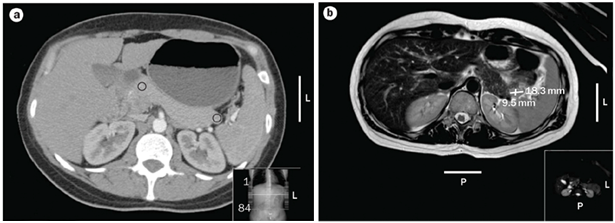

MRI

The latest studies have demonstrated that MRI is superior to other preoperative imaging techniques in identifying small pancreatic insulinoma. Its sensitivity ranges from 85% to 95%, in the detection of insulinoma and the determination of the presence of metastases. Using conventional sequences, small insulinoma usually have a low signal on T1-weighted sequences and a high signal on T2-weighted sequences. Some insulinomas containing fibrous tissue may show low signal intensity on both T1- and T2-weighted images. An improvement in MRI technique is the use of diffusion weighted MRI (DWI-MRI) for abdominal imaging. DWI is an MRI technique that detects changes in the molecular diffusion of water in biologic tissues and the valuable role of DWI in the detection of pancreatic tumors has been reported in several studies (Figure 4A), (Figure 4B) & (Figure 5).33–36

Figure 4 Localization of a possible insulinoma in the case patient. (a) CT scan of the abdomen of the patient described showing nodular pancreas but no differential enhancement after contrast (b) | MRI scan of the abdomen showing a 18.3mm by 9.5mm enhancing islet cell tumor within the tail of the pancreas. 31

Figure 5 Example of the use of MRI in the localisation of insulinoma. (a) T2-weighted image demonstrating a lesion in the tail of the pancreas, less well seen in (b) T1-weighted MRI demonstrating the pancreas in the same patient. 32